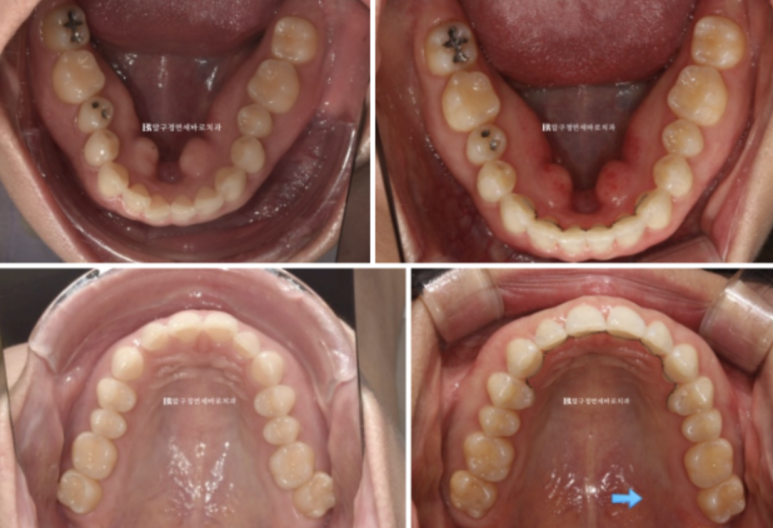

23년 7월부터 23년 12월까지 약 5개월에 걸쳐서 1차세트 장치 14개를 다 착용한 후 모습입니다

23.12

가위교합과 벌어졌던 공간은 이미 해결이 되엇습니다.

중심선도 잘 맞습니다.

블랙 트라이앵글과 치아 사이 미세공간 마무리를 위해 추가적인 제작에 들어갑니다.

가위교합은 1차 세트에서 완전히 개선이 되었기에 미니스크류는 추가장치 제작을 하기로 한 날 제거했습니다.

23.07~24.05

악궁 모양과 배열이 잘 잡혔고 재제작때 미니스크류 뺀 자리는 잘 안물어서 흔적이 없습니다.

흉터가 작게 남는 경우도 있지만 흉터도 남지 않는 경우가 많습니다.